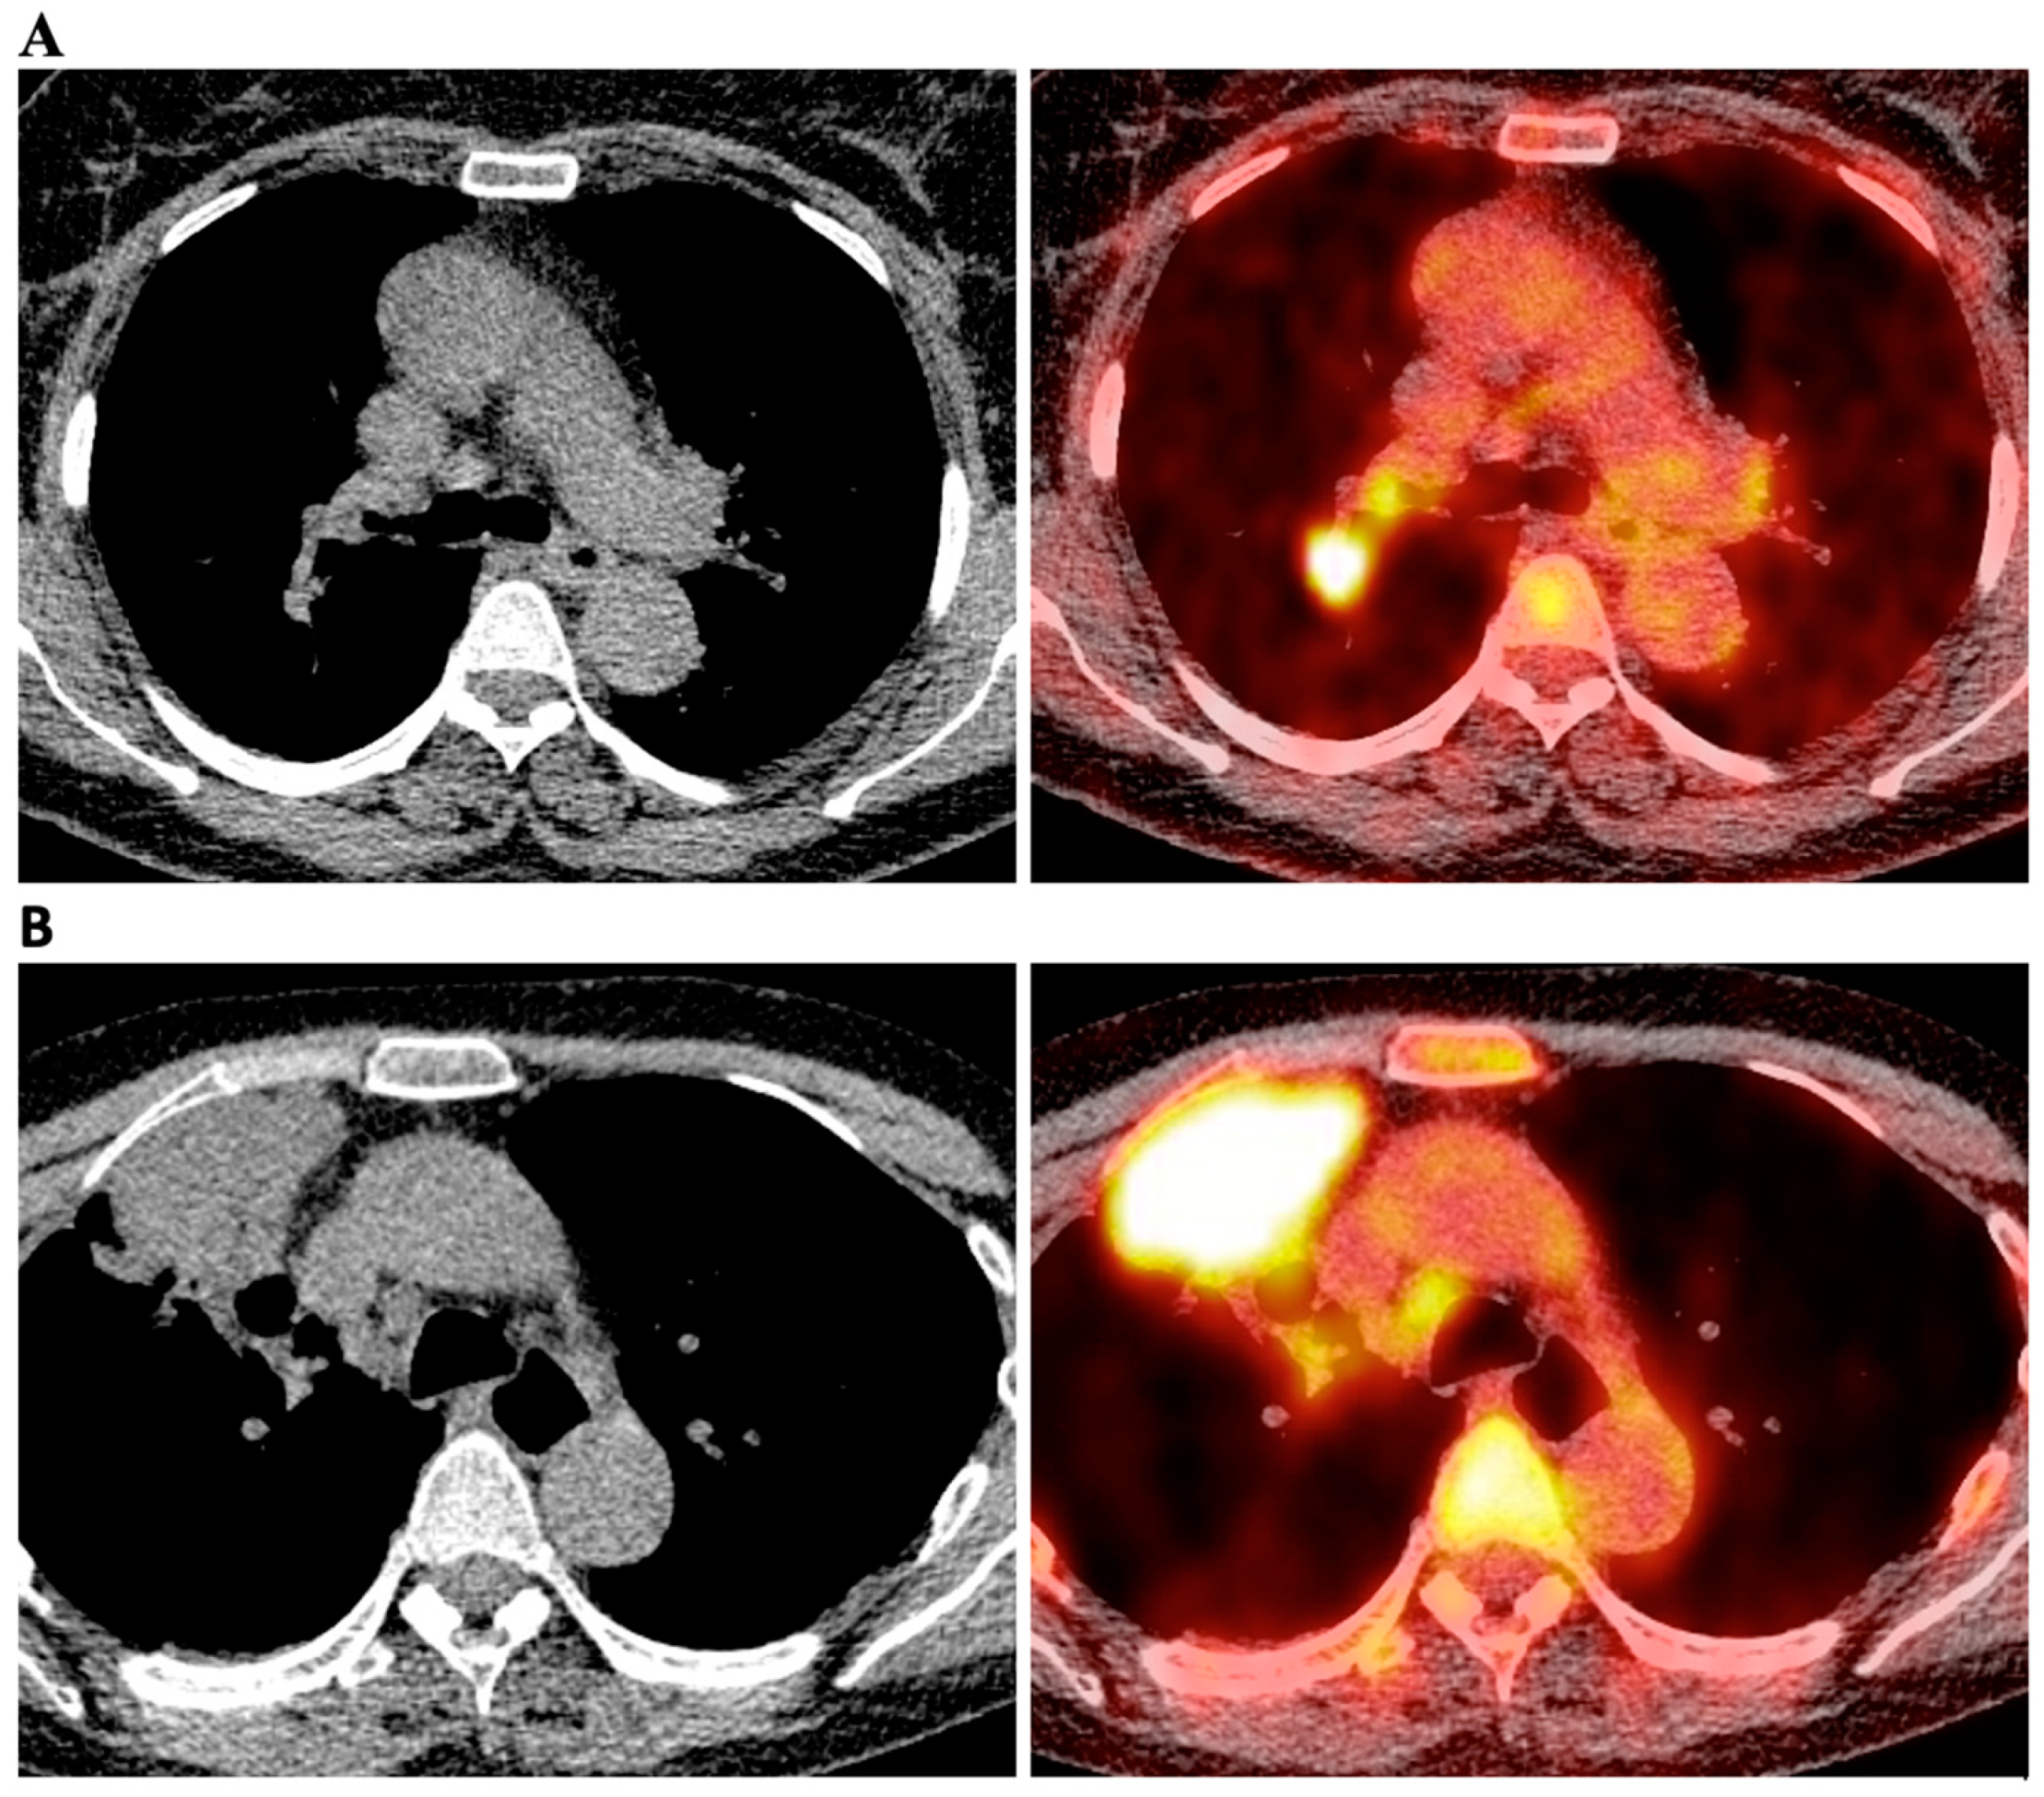

Preoperative Hilar and Mediastinal Lymph Node Staging in Patients with Suspected or Diagnosed Lung Cancer: Accuracy of 18F-FDG-PET/CT:A Retrospective Cohort Study of 138 Patients

2.2. Integrated 18F-FDG PET/CT